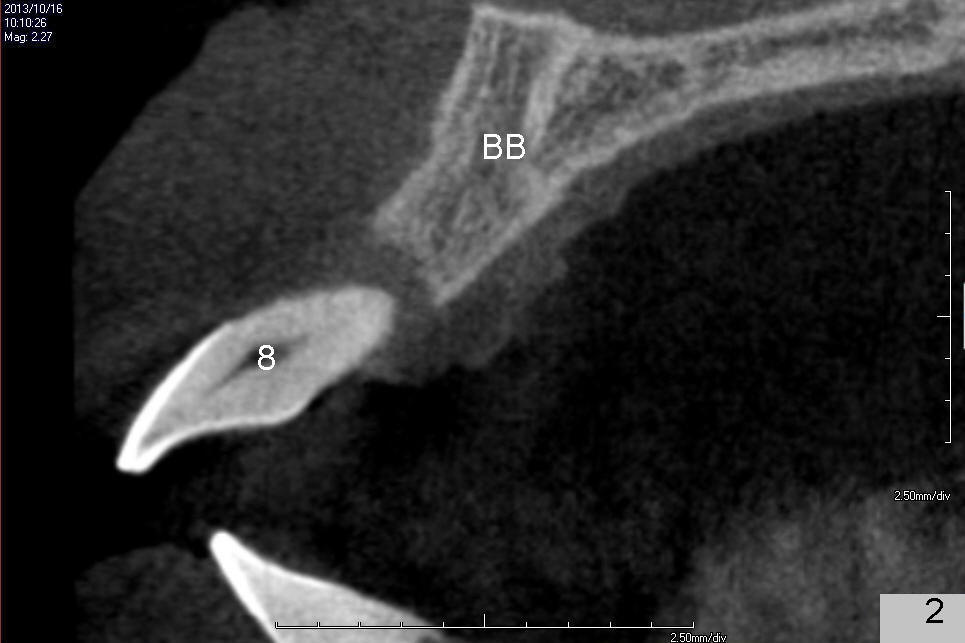

A 49-year-old man has severe chronic periodontitis. The upper central incisors are protrusive and mobile (Fig.1,2: #8,9), but the basal bone is wide and tall (BB in Fig.2). Immediate implants are going to be placed. To avoid malpositioning of the implant, initial osteotomy begins close to the palatal plate (Fig.3: P), while the axis of the osteotomy is parallel to and close to the buccal plate (>). The implant (Fig.4 pink), abutment (red) and the crown (white) will be in a favorable trajectory. To reduce protrusion, the incisal edge of the lower central will be trimmed (compare Fig.3 * and Fig.4 black area).

On the day of surgery, occlusal equilibrium is to be done for the supraerupted, protrusive lower central incisors first. If there is time, scaling and root planing will be done for the lower arch. Temporary abutments will be used to fabricate immediate provisionals. Screws will be used to fix the abutment/provisional complex to avoid cement. The opening for the screw will be closed with cotton pellet and Cavit. How is the result?